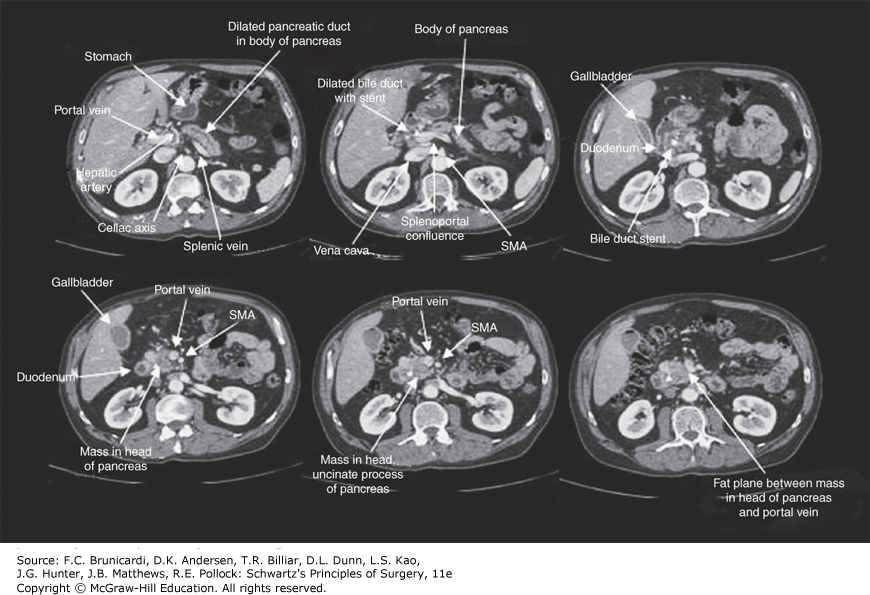

Computed tomography scan demonstrating resectable pancreatic cancer. SMA = superior mesenteric artery.